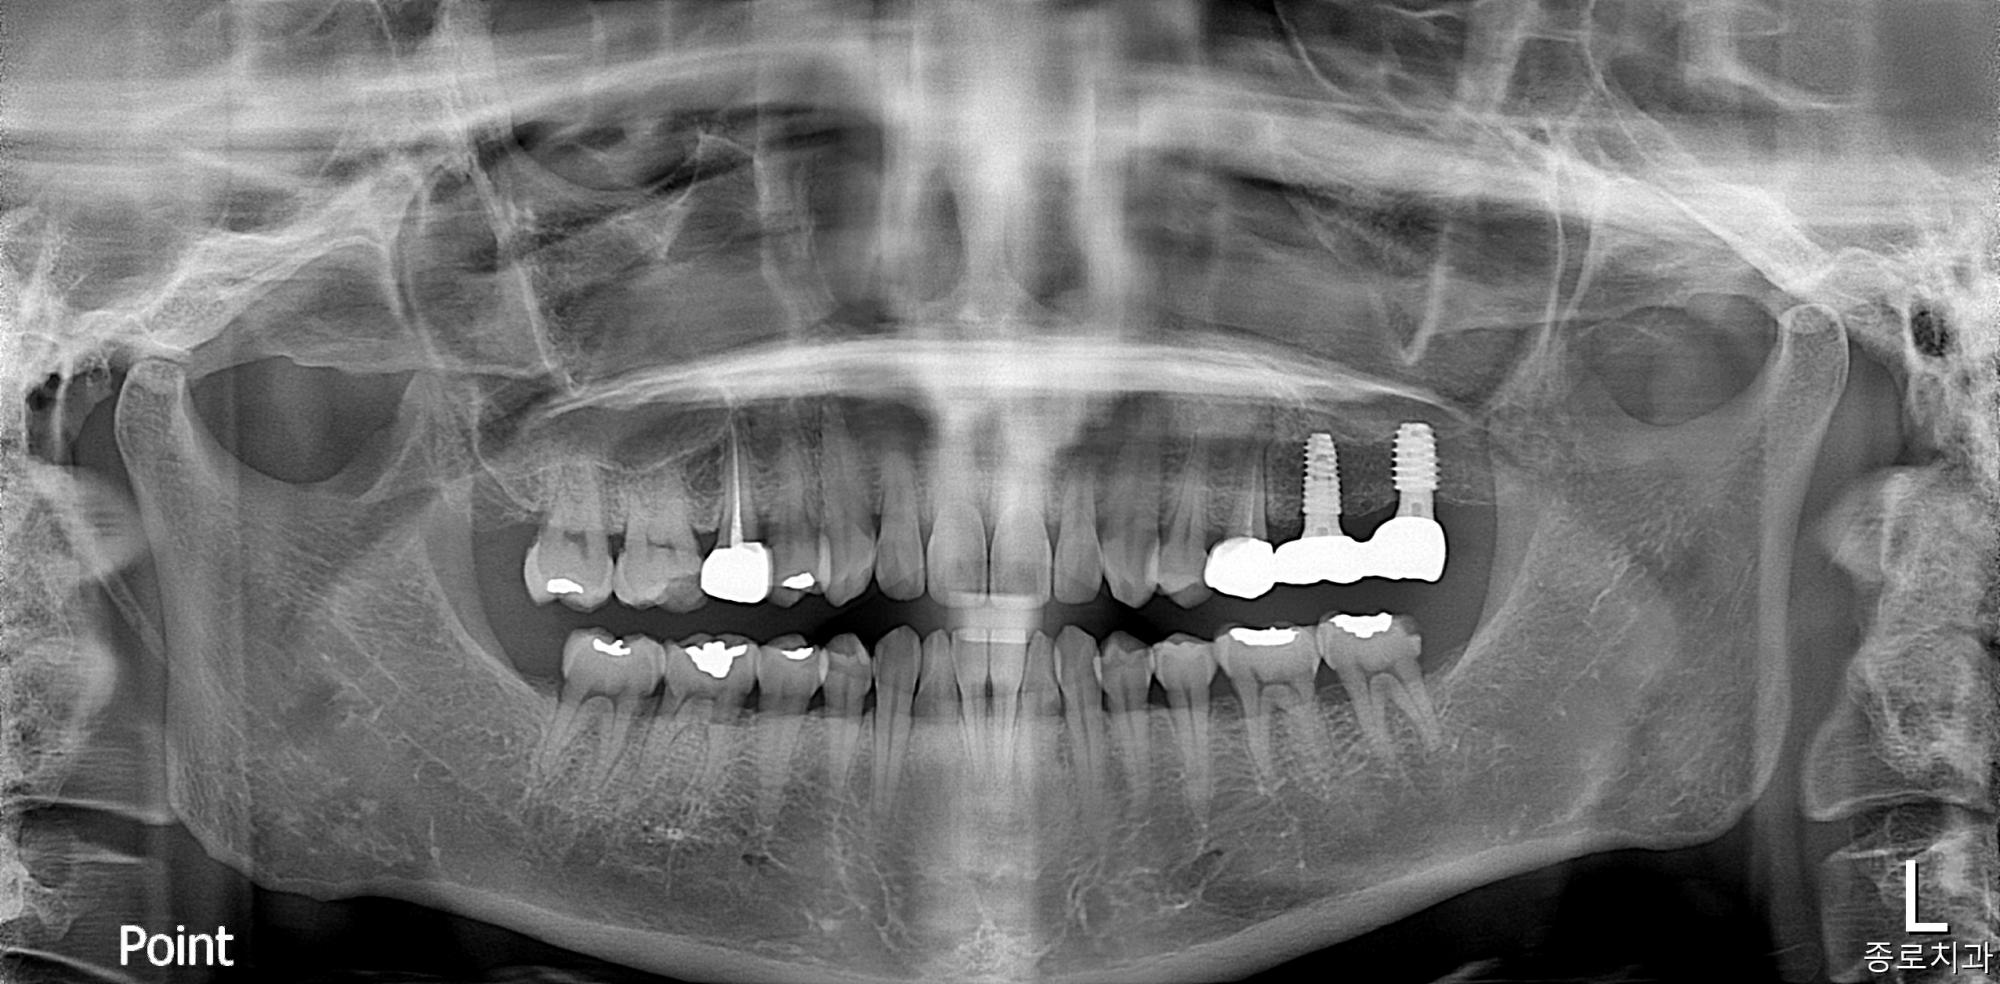

전/후 사진

임플란트

치료 전

치료 후